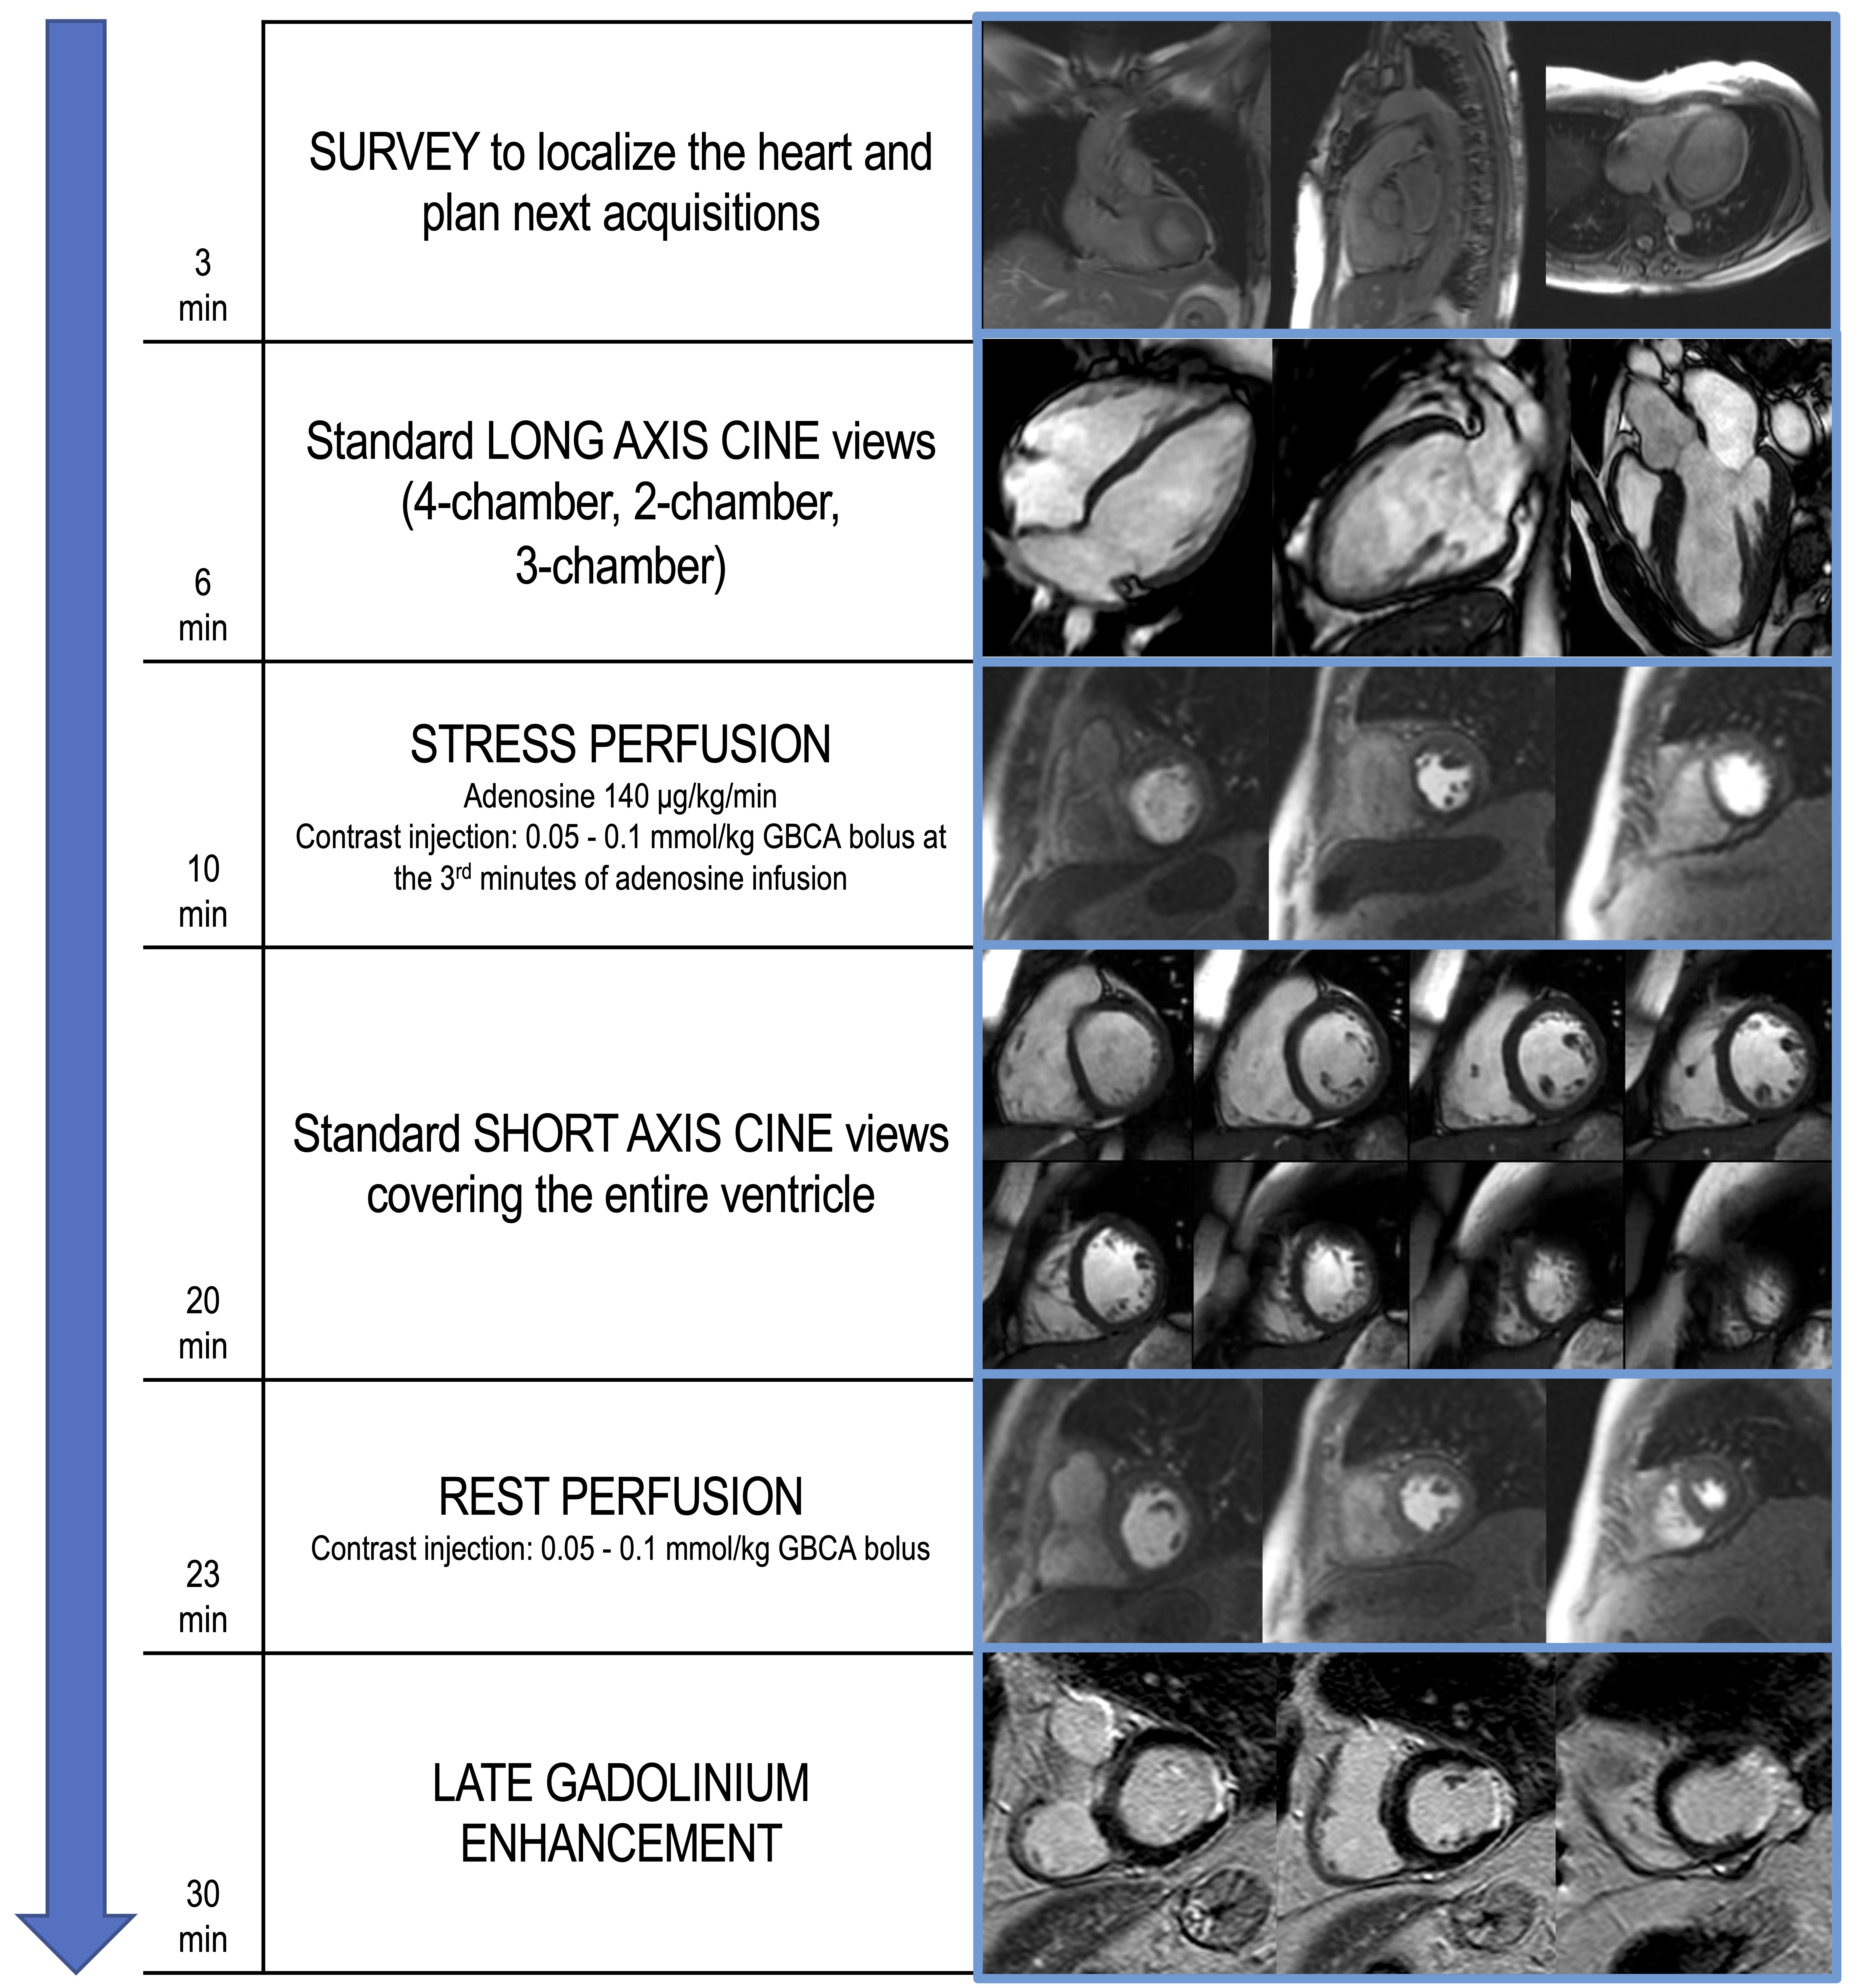

Stress CMR with vasodilators induces a myocardial perfusion defect with the coronary steal phenomenon. During the administration of a vasodilator, the blood flow is increased in regions perfused by normal coronary arteries and reduced in areas supplied by stenotic arteries. Once hyperemia is obtained, serial dynamic stress perfusion images are continuously acquired during administration of intravenous contrast agent. Images are usually acquired in a stack of three short-axis planes covering the entire ventricle and an optional long axis plane. Care should be taken to avoid the inclusion of the LV outflow tract in the most basal short-axis slice. The post-contrast signal enhancement is visualized as the injected gadolinium-based contrast agent enters into cardiac chambers and perfuses the myocardium. In normally perfused myocardial segments, the contrast agent will enter faster and evenly, inducing a quick and higher increase in T1 signal intensity compared to areas supplied by stenotic arteries [28]. Hypoperfused areas will show a segmental subendocardial hypointense stripe (Fig. 1). According to the 2019 ESC guidelines, high event risk in patients with established chronic coronary syndromes is defined by at least 2 of 16 segments with stress perfusion defects [27].

Fig. 1.

Fig. 1.Example of abnormal stress CMR. The first-pass perfusion images are usually acquired in three short axis slices, at the basal (A), mid (B) and apical (C) ventricular level during coronary maximal vasodilation. This example shows an inducible perfusion defect, appearing as a hypointense subendocardial area (indicated by the yellow arrow lines) in the inferior and infero-septal segments. CMR, cardiovascular magnetic resonance.

Fig. 2.

Fig. 2.Example of stress CMR protocol with adenosine. The suggested protocol lasts about 30 min and starts with the acquisition of scout images to localize the heart (3 min). Standard long axis cine images are then acquired in 4-chamber, 2-chamber and 3-chamber orientation (6 min). First-pass perfusion images are therefore acquired in three short axis slices, during hyperemic conditions obtained with the administration of a vasoactive agent (i.e., adenosine), to assess for perfusion defects (10 min). Dosage of adenosine and contrast agent infusion are reported. In the following minutes, short axis cine images covering the entire ventricle are performed (20 min). At least 10 min after stress perfusion, rest perfusion images are acquired (23 min). About 5 min after the 2nd GBCA bolus injection, LGE images are performed, investigating the presence of myocardial scars (30 min). CMR, cardiovascular magnetic resonance; GBCA, gadolinium-based contrast agents; LGE, late gadolinium enhancement.